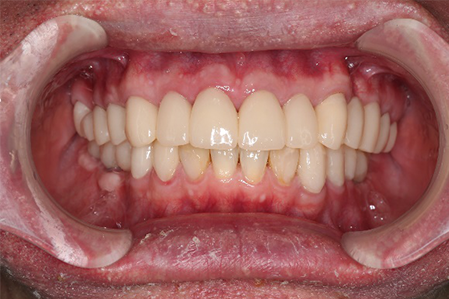

この患者様は長い事歯科医院には通っておらず、下の歯は前歯以外は全て崩壊していることが分かります。

様々なことを鑑み、患者様とも何度も話し合いを行い、下の奥歯には必要最低限のインプラントを、他の歯も外科処置を施しなるべく歯を抜かない方法を取りました。

最終的に抜歯した本数は下の歯5本。上の歯に関しては全て残すことが出来ました。

奥歯があることで前歯の負担を減らし、前歯を失うリスクを下げることが出来ます。

| 治療期間 | 2年 |

| 費用 | 歯周外科治療 3万円×17本 GBR 15万円×2部位 インプラント 37万円×4本 補綴 ジルコニアクラウン 15万円×24本 |